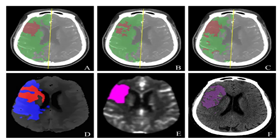

已应用于西医医疗设备医疗诊断和中医诊断,为诊疗提供辅助决策支持。